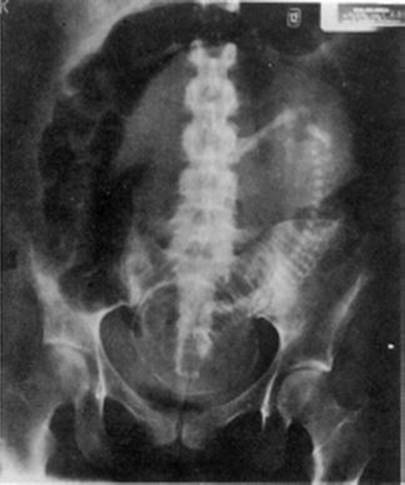

Clinical examination is especially difficult in the third trimester of pregnancy due to enlarged gravid uterus and displacement of intraperitoneal organs. Additional difficulty is that physicians are reluctant to perform initial and repeated plain X-rays of the abdomen which would otherwise be done in nonpregnant patients if indicated. Specific difficulty during the third trimester is dislocation of small and large bowel making radiologic diagnosis more difficult (Fig. 8.1).

Fig. 8.1

Supine X-ray in 30 weeks pregnancy. Gravid uterus displacing gas-filled colon without dilatation [128]